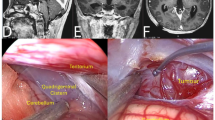

For rats in Groups A and B, the right STN and GP were selected as the targeted nuclei. For rats in Groups C and D, the bilateral STN were selected as target nuclei. Two straight leads were implanted in each rat in Groups A and C, and a curved lead was implanted in each rat in Groups B and D. The effects of curved lead implantation on spatial learning and memory were assessed using MWM tasks. There were no differences between the four groups on the performance during either the acquisition or the probe tests (Fig. 4). At the seventh day post-implantation, the rat brains were obtained and processed for histological analysis. The brain sections stained with H&E staining showed that all of the straight leads and the curved leads were implanted accuratly (Fig. 5).

(a–d) Schematic illustrations of the leads localized in the selected targets. The location of the lead tip of the straight lead was illustrated (a and c). And the location of the lead tip and the point of the curved lead passing through the coronal section 1.08 mm posterior to the bregma (b) or the marker line (2.6 mm mediolateral, black dovetail arrow, (d) were also illustrated. Leads were located within the boundaries of the selected targets in all implanted rats. (e,f) The coronal sections of the brain of a rat in Group C. Two holes were observed at the right GP (figure e, black triangle) and right STN (f) black arrow) respectively, which were caused by an implanted curved lead. (g) The “curved lead pathway” that passing through bilateral STN (black dashed line) could be designed on the coronal section at 3.48 mm posterior to the bregma. It can be observed on the HE stained coronal brain section that the implanted lead (black line) passes the bilateral STN. “Curved lead pathway” crosses the midline, passes through posterior hypothalamus (a) potential target for DBS to ameliorate akinesia in rat42,43) and the upper edge of third ventricle. IVF: interventricular foramen; ic: internal capsule; cp: cerebral peduncle; 3 V: the third ventricle; PH: posterior hypothalamus; Subl: subincertal nucleus. The scale bars represent 500 micrometers. The number at the bottom of each panel corresponds to the distance from bregma in mm, according to the Paxinos and Watson atlas38. Figures a-d and f were modified from The Rat Brain in Stereotaxic Coordinates of Paxinos and Watson40 (reproduced with permission).

However, although the curved leads were located within the boundaries of the STN or GP in all implanted rats, most of the curved leads implanted to the rats of Group D seemed to be a litter higher (with the variations of ≤0.1 mm) than the planned positions.